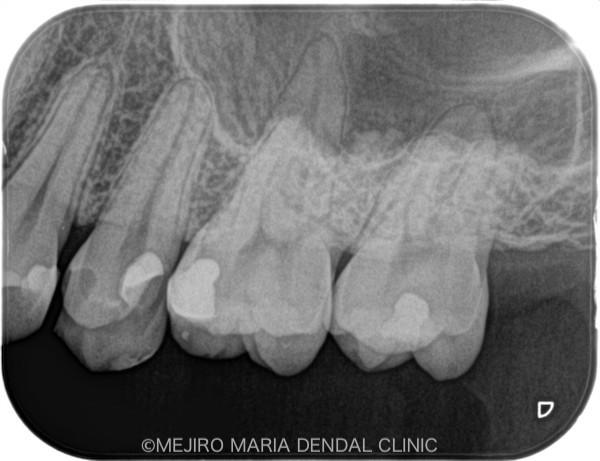

術後2週間経過した時点で、歯髄の反応が正常であることを確認しました。今後は、セラミックインレーを装着する予定です。

目白マリア歯科_【症例】生活歯髄断髄法(生活歯髄療法)による歯髄保存症例(精密根管治療)術前術後レントゲン画像